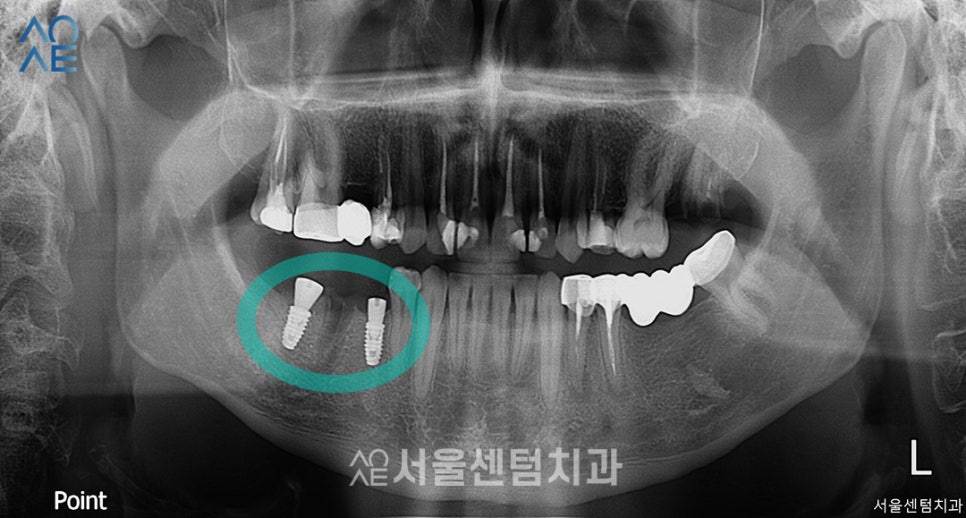

20대 임플란트 식립

(사진상으로는 왼쪽)

오른쪽 아래 어금니를 총 3개 상실한 상태로

내원하셨던 환자분입니다.

기존 브릿지를 제거하고

2개의 임플란트만 식립해도

치아의 기능과 심미성을 모두 회복할거라

진단하였습니다.

다행히 뼈이식이 필요한 상태는 아니라서

별도 추가 진행은 하지 않습니다.

다행히 수술은 무사히 마쳤고

3개월 후에 보철물을 수복하기로 했습니다.